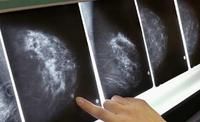

1、乳腺X線檢查:乳腺X線攝影是使用時間最長且較為成熟的方法,對早期乳腺癌的診斷符合率較高,具體包括鉬靶X線乳房攝影和乾板乳房攝影。美國健康保險計畫組織(HIP)普查所發現的乳腺癌中,臨床觸不到腫塊而攝影發現癌灶者占1/3。但其缺點是對一些緻密型乳房顯影不滿意,容易漏掉小的癌灶。